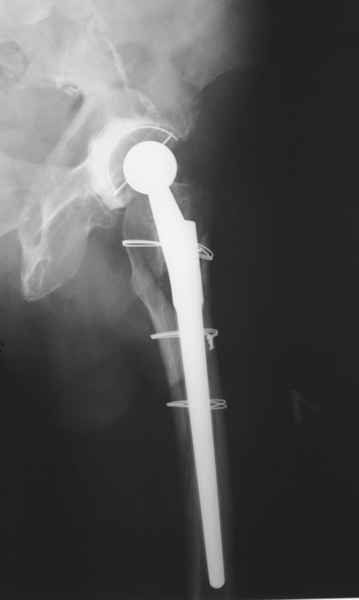

Уважаемые коллеги, продолжая дискуссию, начатую на "Вреденовских чтениях", хочу сказать, что принципиально сущестует два возможных варианта лечения.

1.Остеосинтез на ножке. Мне кажется, что применительно к этому случаю малоперспективный вариант. Синтез хорош, когда можно его выполнить в малоинвазивном исполнении и достигнуть стабильности. Действительно, если ножка б/цементной фиксации после этого не будет иметь фиксации, то ревизия не будет иметь проблем. В представленном случае стабильность синтеза сомнительная, а проведение доп.иммобилизации приведет к контрактуре суставов.

2. Применение ножки дистальной фиксации, мы отдаем предпочтение ножке Вагнера с фиксацией проксимального отдела на ножке. Более травматичное вмешательство, но при стабильной фиксации ножки реабилитация идет в обычном режиме.

Хочется показать два подобных случая, П-ка З. 72 лет и п-т Г. 80 лет. Сразу принимаю замечание, что это были ножки цементной фиксации, просто под руками не было бесцементника.